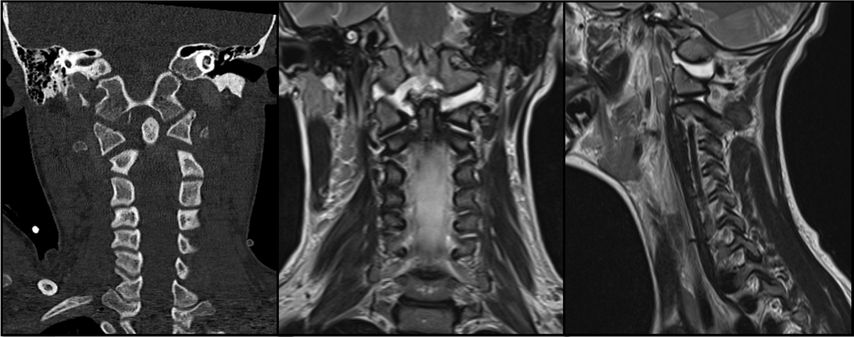

Abb. 2: CT, MRT und Versorgungsstrategie bei einer stark dislozierten Densfraktur Typ IIb mit begleitender Atlasbogenfraktur bei einer geriatrischen Patientin

Etwa 20% aller Wirbelkörperfrakturen im zervikalen Bereich sind Densfrakturen, die typischerweise eine bimodale Altersverteilung aufweisen: Ein kleiner Teil betrifft jüngere, sportlich aktive Männer – die Mehrheit der Betroffenen sind jedoch Frauen über 65 Jahre, welche auf Bodenniveau stürzen.10 Die Mortalität dieser Verletzungen kann mit jener von Schenkelhalsfrakturen im geriatrischen Kollektiv verglichen werden und beträgt rund 14% nach 30 Tagen sowie 44% nach zwei Jahren.11 Eine bestehende Arthrose des atlantoaxialen Gelenks, degenerative subchondrale zystische Veränderungen des Dens sowie eine verminderte Beweglichkeit der subaxialen Wirbelsäule bei geriatrischen Patient:innen erhöhen die mechanische Belastung auf die oberen Segmente der Halswirbelsäule.12 Dies begünstigt an der biomechanischen Schwachstelle – der Densbasis – das Auftreten einer Fraktur.10 Die Klassifikation nach Anderson und D’Alonzo, modifiziert durch Grauer, hat sich aufgrund ihrer prognostischen und therapeutischen Relevanz als Standard für die Einteilung der Densfrakturen etabliert.13,14 Typ I ist eine Abrissfraktur der Ligamenta alaria an der Densspitze, gilt als stabil und wird in der Regel konservativ behandelt. Typ II betrifft den Übergangsbereich des Dens zum Corpus und ist mit Abstand die häufigste Densfraktur, welche als potenziell instabil gilt. Grauer unterscheidet innerhalb der Typ-II-Frakturen die Subtypen IIa (transversaler Frakturverlauf), IIb (Frakturverlauf von anterosuperior nach posteroinferior) und IIc (von anteroinferior nach posterosuperior). Typ III sind Frakturen des Corpus der Axis, welche in der Regel konservativ behandelt werden können. Die Behandlung der Typ-II-Densfraktur bei älteren Patient:innen wird nach wie vor kontrovers diskutiert. Während einige Studien eine operative Versorgung zur Verbesserung der Fusionsrate sowie der Lebensqualität empfehlen, weisen andere darauf hin, dass auch eine konservative Therapie bei geriatrischen Patient:innen ein zufriedenstellendes funktionelles Ergebnis und eine geringe Komplikationsrate ermöglichen kann.11 Die Operationsindikation ergibt sich bei nachgewiesener Instabilität oder bei neurologischer Verschlechterung, etwa infolge einer Myelopathie. Zu berücksichtigen ist, dass bei konservativer Behandlung das Risiko einer Pseudarthrose mit daraus resultierenden chronischen Beschwerden sowie einer möglichen progredienten neurologischen Verschlechterung besonders bei aktiven älteren Patient:innen erhöht ist. Die Blutversorgung des Dens erfolgt überwiegend durch ein Gefäßnetz aus aufsteigenden Ästen der A. vertebralis, das an der Spitze des Dens eine Anastomose und an der Basis einen Gefäßplexus bildet. Diese Gefäßversorgung wird bei Typ-II-Frakturen häufig unterbrochen, was die Knochenheilung negativ beeinflusst.15 Für die Beurteilung der Instabilität gelten folgende Kriterien: eine Dislokation von mehr als 5mm, ein Frakturspalt von über 2mm oder ein kyphotischer Winkel von mehr als 11°.10 Frische IIa- und IIb-Densfrakturen eignen sich für eine ventrale Schraubenosteosynthese. Die dorsale Fusion wird hingegen für IIc-Frakturen, Trümmerbrüche des Dens, stark dislozierte Frakturen sowie bei bereits bestehender Pseudoarthrose bevorzugt.15 Der Halo-Fixateur wird bei geriatrischen Patient:innen heute nicht mehr empfohlen,5,10,11,15 da die Komplikationsrate mit über 30% sehr hoch ist. Häufige Komplikationen umfassen Aspirationspneumonien, Infektionen der Pin-Stellen sowie Druckstellen, Schluckbeschwerden und eine insgesamt erhöhte Mortalität.